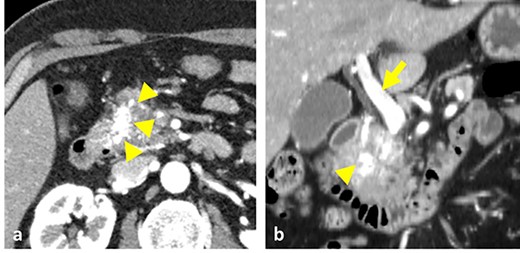

A 54-year-old man was admitted to our hospital presenting with acute upper abdominal pain. He had no family history of pancreatitis, hereditary disease or abdominal trauma; however, he had a history of habitual alcohol consumption. Blood tests showed an elevated white blood cell count (16 900/μl), serum amylase (260 U/l) and lipase (337 U/l). Contrast-enhanced computed tomography (CT) revealed meandering vessels in the pancreatic head. These vessels were enhanced in both the arterial and portal phases, while the portal vein was enhanced in the arterial phase. Swelling of the pancreatic head suggested the development of pancreatitis (Fig. 1). Three-dimensional CT revealed blood vessel communications between the arteries and veins in the pancreas (Fig. 2). Endoscopic ultrasonography (EUS) also revealed meandering vessels in the pancreatic head surrounded by low echoic lesions with diameters of 8 mm (Fig. 3). Magnetic resonance imaging (MRI) revealed flow voids and a cyst measuring 8 mm in diameter at the pancreatic head. Neither stenosis nor dilation of the main pancreatic duct was observed.

Contrast-enhanced CT images. (a) Vessels in the pancreatic head were strongly enhanced during the arterial phase (arrowheads). (b) Both the vessels in the pancreas head (arrowhead) and the portal vein (arrow) were enhanced at the arterial phase.